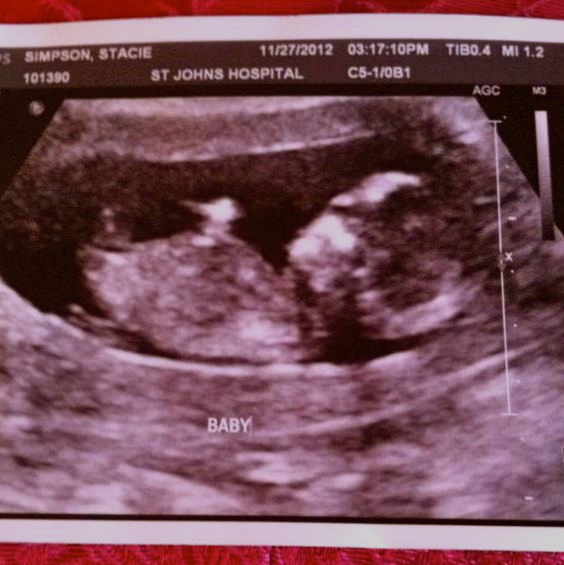

Hello. What are your gender guesses ladies and gentlemen? Thanks in advance.

Attachment 7730Attachment 7730Attachment 7730

Thanks for your responses. Is that a nub sticking straight up at the base?